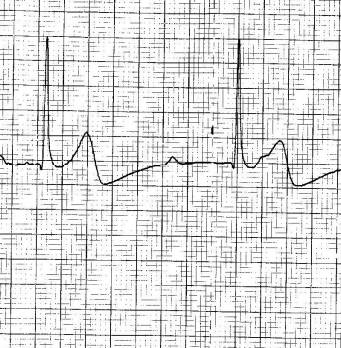

Vous le savez certainement, le canton de Fribourg est précurseur en terme de "premiers répondants" équipés d'AED permettant de prodiguer le plus précocement possible, les premiers soins aux victimes d'arrêts cardio-resp…